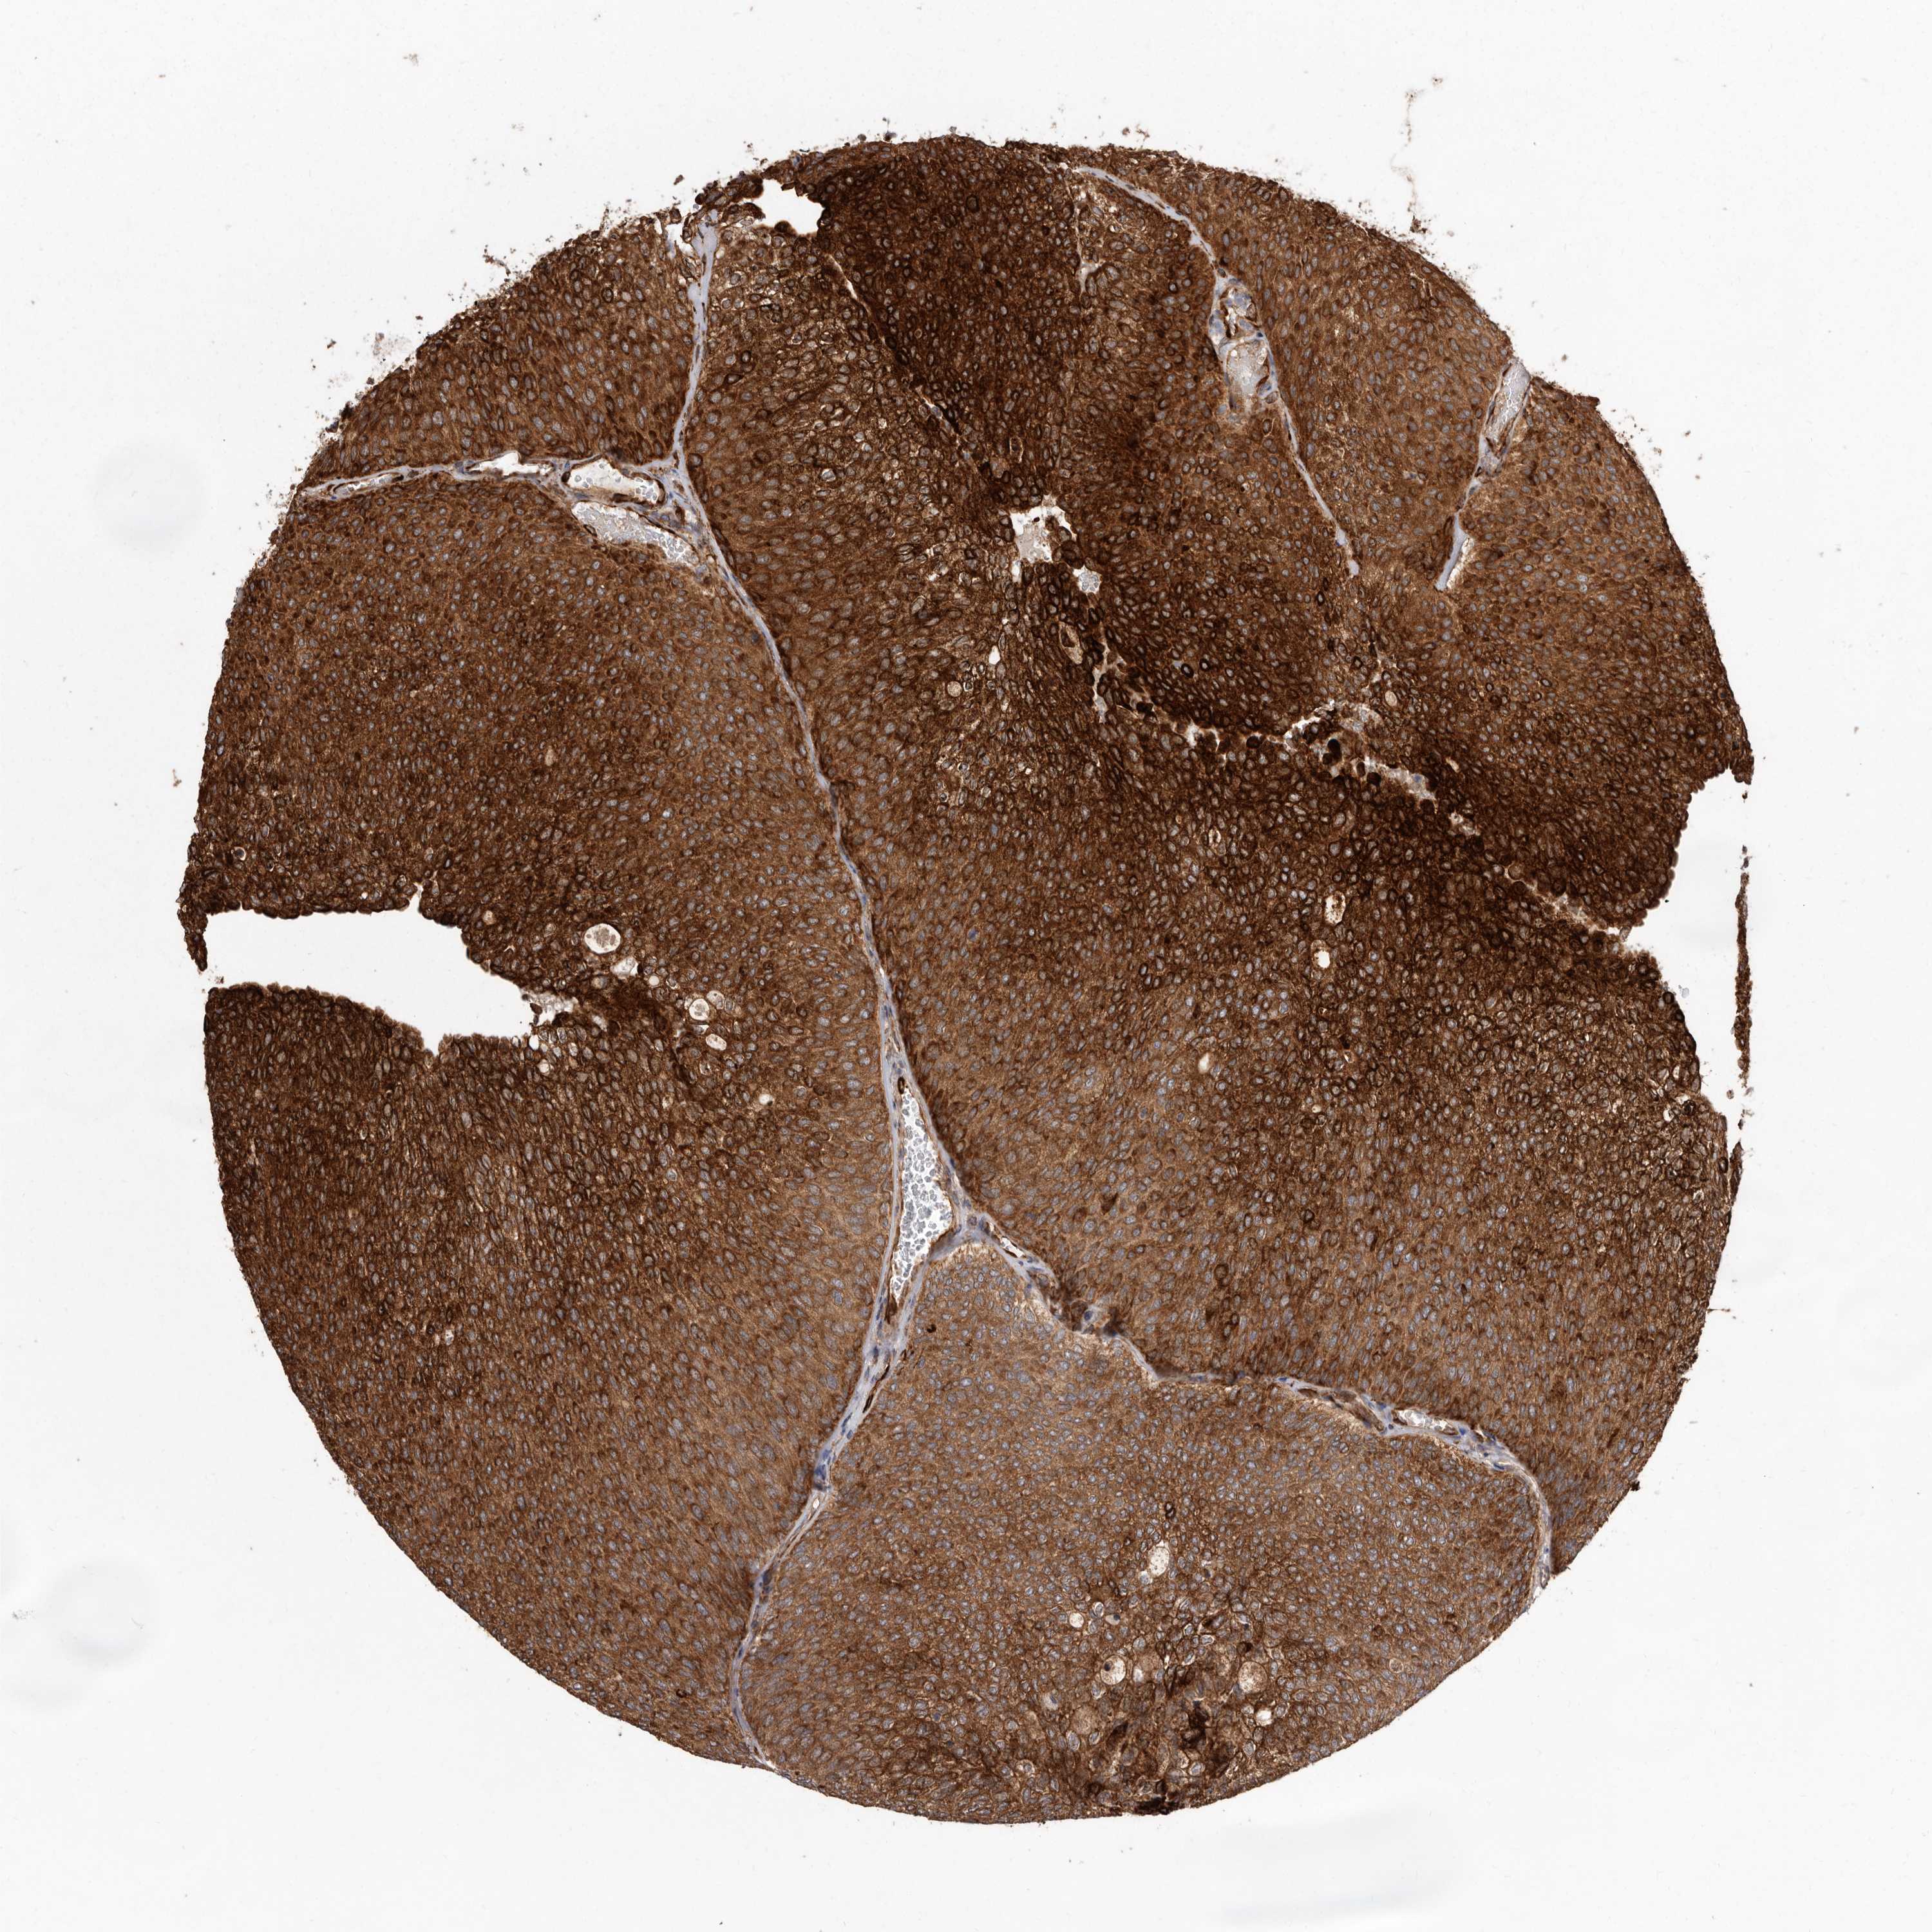

UROTHELIAL CANCER - Protein expressioni

A mouse-over function shows sample information and annotation data. Click on an image to view it in a full screen mode. Samples can be filtered based on level of antibody staining by selecting one or several of the following categories: high, medium, low and not detected. The assay and annotation is described here.

Note that samples used for immunohistochemistry by the Human Protein Atlas do not correspond to samples in the TCGA dataset.

Antibody stainingi

Antibody staining in the annotated cell types in the current human tissue is reported as not detected, low, medium, or high, based on conventional immunohistochemistry profiling in selected tissues. This score is based on the combination of the staining intensity and fraction of stained cells.

Each image is clickable and will lead to virtual microscopy that enables deeper exploration of all samples and also displays staining intensity scores, fraction scores and subcellular localization as well as patient and tissue information for each sample.

Antibody HPA028476

Antibody HPA028486

Antibody HPA028563

Urothelial carcinoma, Low grade

Urothelial carcinoma, High grade